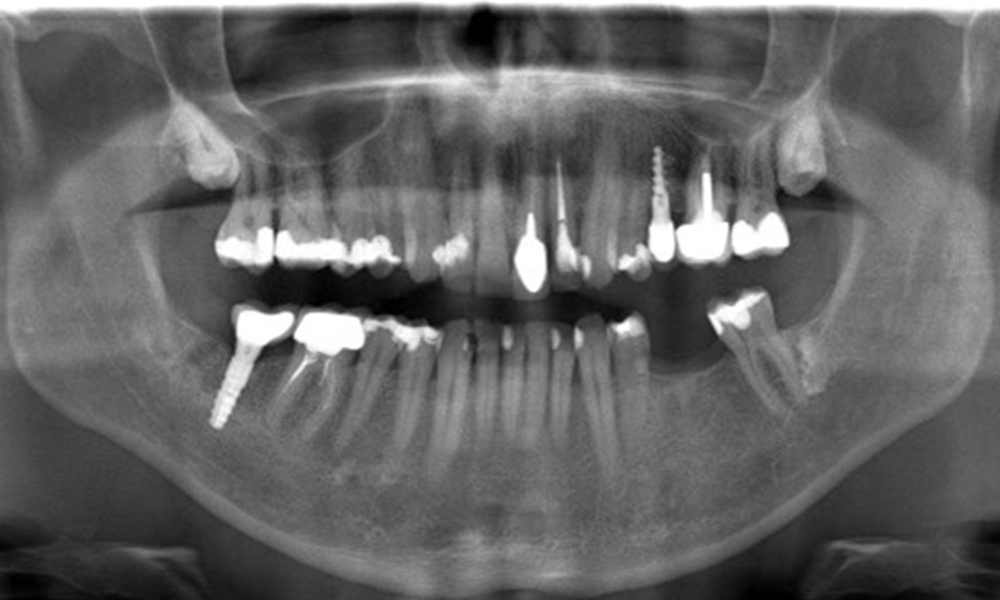

OPG: 29.02.2024

Der Patient hat einige zahnärztliche Restaurationen und zwei Implantate (2. und 4. Quadrant). Anhand der aktuellen Befunde lässt sich eine Gingivitis bei stabilem parodontalen Zustand am reduzierten Parodont (Stadium III, Grad A) feststellen.

Versorgungen: zahnärztliche Restaurationen (NEM keramisch verblendet), zwei Implantate (2., 4. Quadrant)